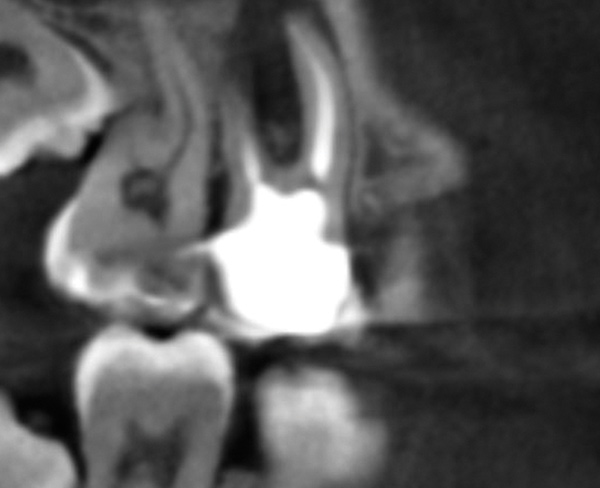

CBCT can be used to aid in further assessment of a previously endodontically treated tooth. A study by Uraba et al demonstrated that CBCT imaging is 20% more effective in detecting periapical lesions that cannot be detected on a periapical radiograph (Figure 1 and Figure 2).7 Diagnostic CBCT can provide additional information in comparison to periapical radiographs when treatment planning an endodontic retreatment case.8 The use of a limited field of view (FOV) CBCT on a patient that presents with a problem on an existing endodontically treated tooth can allow the clinician to critically evaluate the quality of the existing canal(s) obturation, identify any missed canals, and assess the extensiveness of a periapical lesion.

Periapical radiograph of tooth N o. 14 does not definitively reveal

a periapical radiolucency.

Fig 1.

CBCT of the same tooth N o. 14 (palatal

view exposure) shown in Fig 1 definitively shows a periapical lesion.

Fig 2.